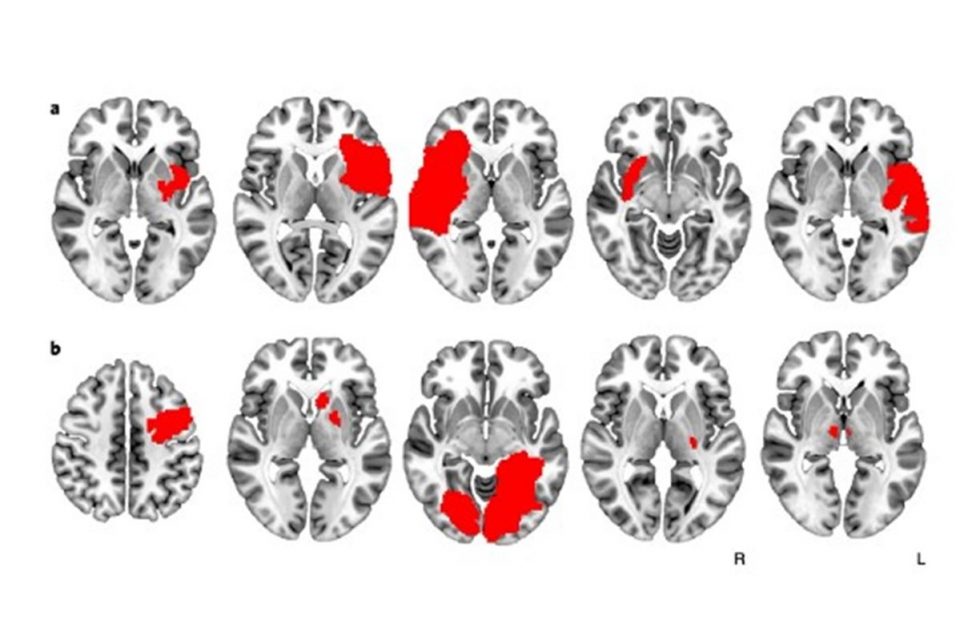

Pesquisadores finlandeses e americanos das universidades de Turku e Harvard se uniram para tentar entender por que alguns pacientes fumantes parecem perder a dependência da nicotina depois de sofrer um AVC ou lesões na cabeça.O estudo, publicado na revista científica Nature Medicine nessa segunda (13/6), investigou as regiões do cérebro que podem estar relacionadas ao vício em nicotina, e os cientistas descobriram que, na verdade, não é só um pedaço do órgão o responsável pelo problema: um circuito de áreas ligadas por fibras neurais parece estar diretamente ligado com a necessidade de buscar a substância presente nos cigarros.“Um dos maiores problemas com o vício é que não sabemos exatamente onde no cérebro deveríamos mirar com o tratamento. Esperamos que, depois dessa pesquisa, tenhamos uma boa ideia das regiões e redes envolvidas”, explica o neurologista Juho Joutsa, um dos autores do estudo, ao jornal The New York Times.Os cientistas usaram técnicas de estatística para analisar exames cerebrais de fumantes que sofreram lesões no cérebro. Um estudo anterior havia verificado que os pacientes com danos na região chamada de ínsula tinham maior chance de parar de fumar.Observando os exames pixel por pixel, Joutsa e seus colegas perceberam que pessoas que não tiveram lesão na região também parecem ter perdido a vontade de fumar. Dados de outros pacientes foram adicionados, e os pesquisadores desistiram de procurar uma região específica — a saída foi analisar diagramas de conexões neurais para entender como a atividade em uma região se relaciona com estímulos em outras.Os pesquisadores conseguiram localizar redes que conectam várias regiões do cérebro onde as lesões tiveram ação imediata na necessidade por nicotina, e outras que não fizeram diferença para o paciente. Os indivíduos que tiveram lesões e pararam de fumar o fizeram imediatamente: nenhum deles sentiu vontade de acender um cigarro e nem o fez nos meses seguintes.As áreas identificadas também parecem ter ação contra o vício em álcool, abrindo portas para o tratamento de qualquer dependência. Alguns especialistas que revisaram o estudo afirmam que partes dos sistemas identificados são usados no tratamento de transtorno obsessivo compulsivo (TOC) e depressão.“O que estamos percebendo é que nossos alvos terapêuticos não são regiões do cérebro, como acreditávamos, mas circuitos conectados. Se levarmos em conta as maneiras como o cérebro se relaciona, podemos melhorar o tratamento”, explica o neurologista Michael Fox, que também assina o estudo.A ideia é usar estimulação elétrica superficial ou até profunda para mimetizar os efeitos de um AVC ou lesão cerebral para que o paciente deixe de precisar da nicotina. Uma região específica, o córtex medial frontopolar, parece ser uma área cheia de conexões e uma boa candidata à estimulação.Os cientistas ponderam que nem todos os cérebros se conectam de maneira igual, e pode ser necessário mapear o órgão de cada paciente para ter certeza de onde aplicar a terapia. Também não se sabe qual seria a frequência do tratamento, e quanto tempo ele duraria.Ainda assim, o professor de psiquiatria Thomas McLellan, da Universidade da Pennsylvania, nos Estados Unidos, considera que o estudo pode ser um dos mais importantes publicados na última década sobre o assunto.“Ele desmente muitos estereótipos que ainda contaminam o campo do vício: que é algo decorrente de problemas de criação, ligado à personalidade fraca ou falta de moral”, afirma. Ele não fez parte da pesquisa.Receba notícias do Metrópoles no seu Telegram e fique por dentro de tudo! Basta acessar o canal: https://t.me/metropolesurgente.Fonte: Metrópoles

Pesquisadores finlandeses e americanos das universidades de Turku e Harvard se uniram para tentar entender por que alguns pacientes fumantes parecem perder a dependência da nicotina depois de sofrer um AVC ou lesões na cabeça.O estudo, publicado na revista científica Nature Medicine nessa segunda (13/6), investigou as regiões do cérebro que podem estar relacionadas ao vício em nicotina, e os cientistas descobriram que, na verdade, não é só um pedaço do órgão o responsável pelo problema: um circuito de áreas ligadas por fibras neurais parece estar diretamente ligado com a necessidade de buscar a substância presente nos cigarros.“Um dos maiores problemas com o vício é que não sabemos exatamente onde no cérebro deveríamos mirar com o tratamento. Esperamos que, depois dessa pesquisa, tenhamos uma boa ideia das regiões e redes envolvidas”, explica o neurologista Juho Joutsa, um dos autores do estudo, ao jornal The New York Times.Os cientistas usaram técnicas de estatística para analisar exames cerebrais de fumantes que sofreram lesões no cérebro. Um estudo anterior havia verificado que os pacientes com danos na região chamada de ínsula tinham maior chance de parar de fumar.Observando os exames pixel por pixel, Joutsa e seus colegas perceberam que pessoas que não tiveram lesão na região também parecem ter perdido a vontade de fumar. Dados de outros pacientes foram adicionados, e os pesquisadores desistiram de procurar uma região específica — a saída foi analisar diagramas de conexões neurais para entender como a atividade em uma região se relaciona com estímulos em outras.Os pesquisadores conseguiram localizar redes que conectam várias regiões do cérebro onde as lesões tiveram ação imediata na necessidade por nicotina, e outras que não fizeram diferença para o paciente. Os indivíduos que tiveram lesões e pararam de fumar o fizeram imediatamente: nenhum deles sentiu vontade de acender um cigarro e nem o fez nos meses seguintes.As áreas identificadas também parecem ter ação contra o vício em álcool, abrindo portas para o tratamento de qualquer dependência. Alguns especialistas que revisaram o estudo afirmam que partes dos sistemas identificados são usados no tratamento de transtorno obsessivo compulsivo (TOC) e depressão.“O que estamos percebendo é que nossos alvos terapêuticos não são regiões do cérebro, como acreditávamos, mas circuitos conectados. Se levarmos em conta as maneiras como o cérebro se relaciona, podemos melhorar o tratamento”, explica o neurologista Michael Fox, que também assina o estudo.A ideia é usar estimulação elétrica superficial ou até profunda para mimetizar os efeitos de um AVC ou lesão cerebral para que o paciente deixe de precisar da nicotina. Uma região específica, o córtex medial frontopolar, parece ser uma área cheia de conexões e uma boa candidata à estimulação.Os cientistas ponderam que nem todos os cérebros se conectam de maneira igual, e pode ser necessário mapear o órgão de cada paciente para ter certeza de onde aplicar a terapia. Também não se sabe qual seria a frequência do tratamento, e quanto tempo ele duraria.Ainda assim, o professor de psiquiatria Thomas McLellan, da Universidade da Pennsylvania, nos Estados Unidos, considera que o estudo pode ser um dos mais importantes publicados na última década sobre o assunto.“Ele desmente muitos estereótipos que ainda contaminam o campo do vício: que é algo decorrente de problemas de criação, ligado à personalidade fraca ou falta de moral”, afirma. Ele não fez parte da pesquisa.Receba notícias do Metrópoles no seu Telegram e fique por dentro de tudo! Basta acessar o canal: https://t.me/metropolesurgente.Fonte: Metrópoles